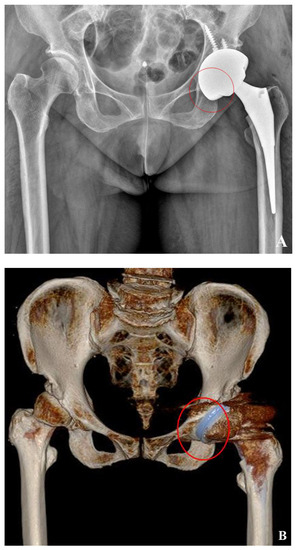

2.4. Cup Position and Fixation

3.2. Cup Position and Fixation

3.3. Correlation of Three Methods of Host Bone Coverage